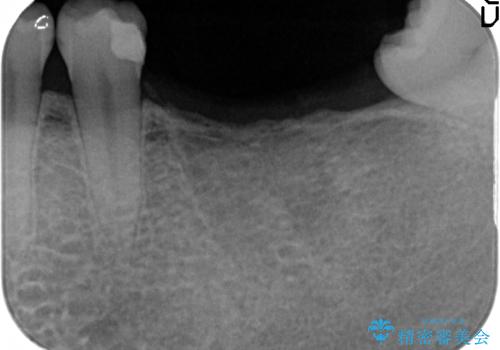

- 数年前に左下の奥歯を2本失ってから物が咬めないため何とかして欲しいと当院にいらっしゃった方の症例です。

左下にインプラント(ストローマン)を2本埋入し、オールセラミッククラウンによる補綴を行いました。